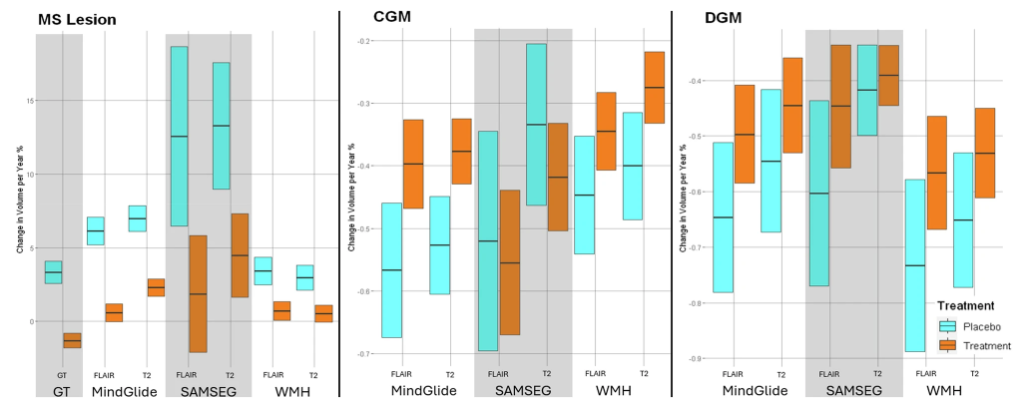

随后,研究人员进行了针对病变治疗效果的纵向验证,涉及多项实验,证明了 MindGlide 在治疗效果检测方面的有效性,如在 SPMS 和 PPMS 试验中,治疗组的病变体积累积量低于安慰剂组;在儿科队列中,MindGlide 成功检测了不同治疗组中病变体积的不同变化,如下图所示。

常规护理儿科数据集中脑区域和病变体积的纵向变化

在此之后,研究人员继续在 PPMS 临床实验中比较了 MindGlide 与其他分割工具和真实病变的治疗效果。实验结果显示 MindGlide 与基础真值非常接近,相比之下, SAMSEG 高估了治疗效果,WHM-Synthseg 则低估了治疗效果,表明了 MindGlide 的病变体积估计精度更高。

下图显示了三者对区域脑容量的评估,结果显示,与纵向 SAMSEG 或 WHM-Synthseg 获得的测量结果相比,MindGlide 的测量结果显示治疗组之间的治疗效果更好。

MindGlide、SAMSEG、WHM-Synthseg 纵向脑区变化及病灶体积比较